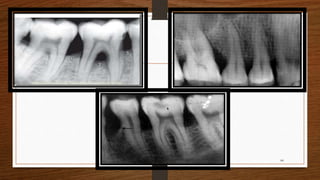

Radio graphical Diagnosis

Widening of PDL space

Loss of corticated interdental crestal margin

Localised or generalized loss of alveolar supporting bone.

Blunting of the alveolar crest due to beginning of bone resorption

Bone loss may be either horizontal or vertical.